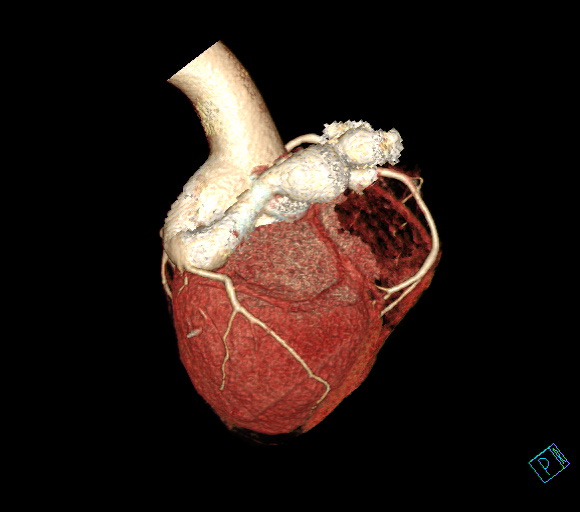

受术患者是一名31岁的小伙子,活动后出现胸闷不适,发作时伴有气促、恶心不适,安静休息后症状缓解,活动后症状再次出现,患者未予重视,未就医治疗,期间症状仍反复发作,严重影响日常生活。在亲戚的介绍下,他慕名来到我院心血管内科就诊,心血管内科主治医师朱建峰接诊后为患者行冠状动脉造影术,检查提示巨大左冠状动脉右房瘘,瘘道最窄处约10cm,心脏超声提示左心室增大。

图:患者术前

心血管内科主任蔡国才分析,患者冠状动脉因异常瘘道血液分流,导致前降支远端血流量锐减,引起“窃血现象”,出现胸闷等症状,若不及时处理,长此以往还会加重循环系统工作负荷,导致肺动脉高压、心力衰竭。内科药物保守治疗效果差;外科手术需要开胸,手术创伤大、风险较高、费用高。